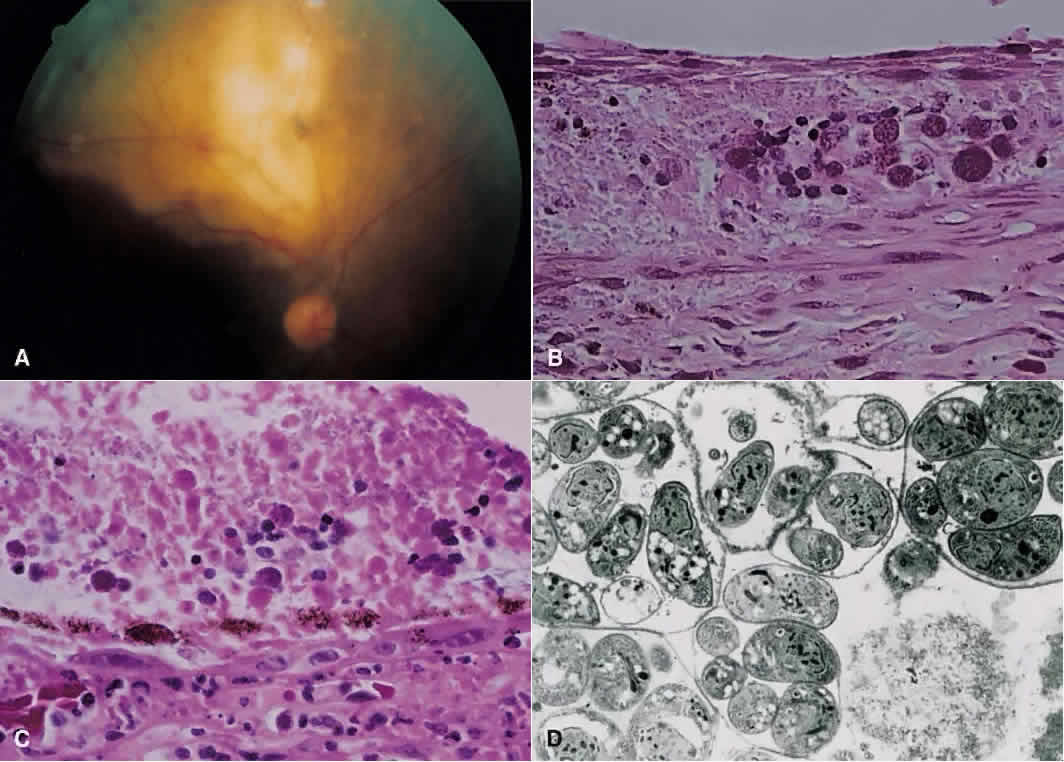

TOXOPLASMOSIS RETINOCHOROIDITIS. Toxoplasmosis accounts for 1% to 5% of AIDS-related retinal infections and usually is acquired as opposed to being congenital.110 Toxoplasmosis in the immunocompromised host differs in its clinical manifestations to that of the immunocompetent host. There tends to be less intraocular inflammation, lack of a preexisting pigmented chorioretinal lesion, and larger, more hemorrhagic areas of involvement, which may be bilateral.110–112 Histopathologic analysis of cases of toxoplasmosis in patients with AIDS shows the presence of Toxoplasma cysts, necrosis of the retina, and a minimal lymphocytic infiltrate within all layers of the retina (Fig. 13).110 In addition, the choroid shows the presence of histiocytes, plasma cells, and eosinophils.113

Fig. 13 A. Right fundus from patient with the acquired immunodeficiency syndrome showing a large area of necrotizing retinitis (pigmentation within area of necrosis, possibly representing previous site of activity) with hemorrhage, which, on histopathologic analysis (B and C), revealed retinal necrosis and the presence of cysts consistent with Toxoplasma gondii (hematoxylin and eosin; B × 200, C × 500). D. Electron microscopy shows tachyzoites within cysts.